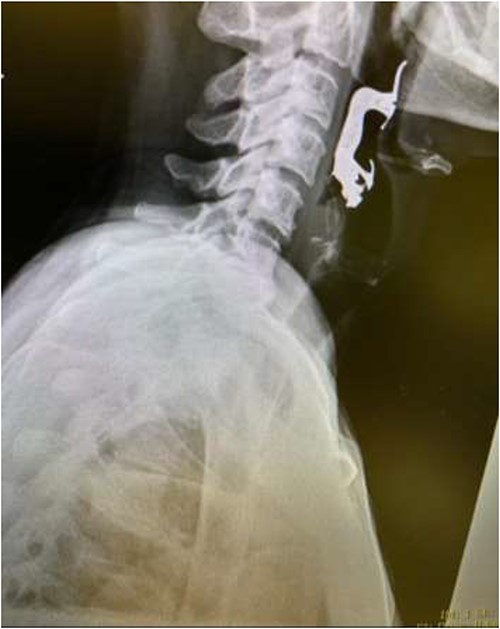

The final case is of a 75-year-old female who presented to hospital after inhalation of her dentures (Figs 6 and 7). After discussion with the anaesthetic team, apnoeic oxygenation was once again utilized in order to remove the foreign body without risk of dislodgement and to decrease the risk of a potential surgical airway (Fig. 8).

Lateral neck X-ray showing radio-opaque object in the upper airway.

Anterior-posterior neck X-ray showing a radio-opaque object, in keeping with metal dentures.